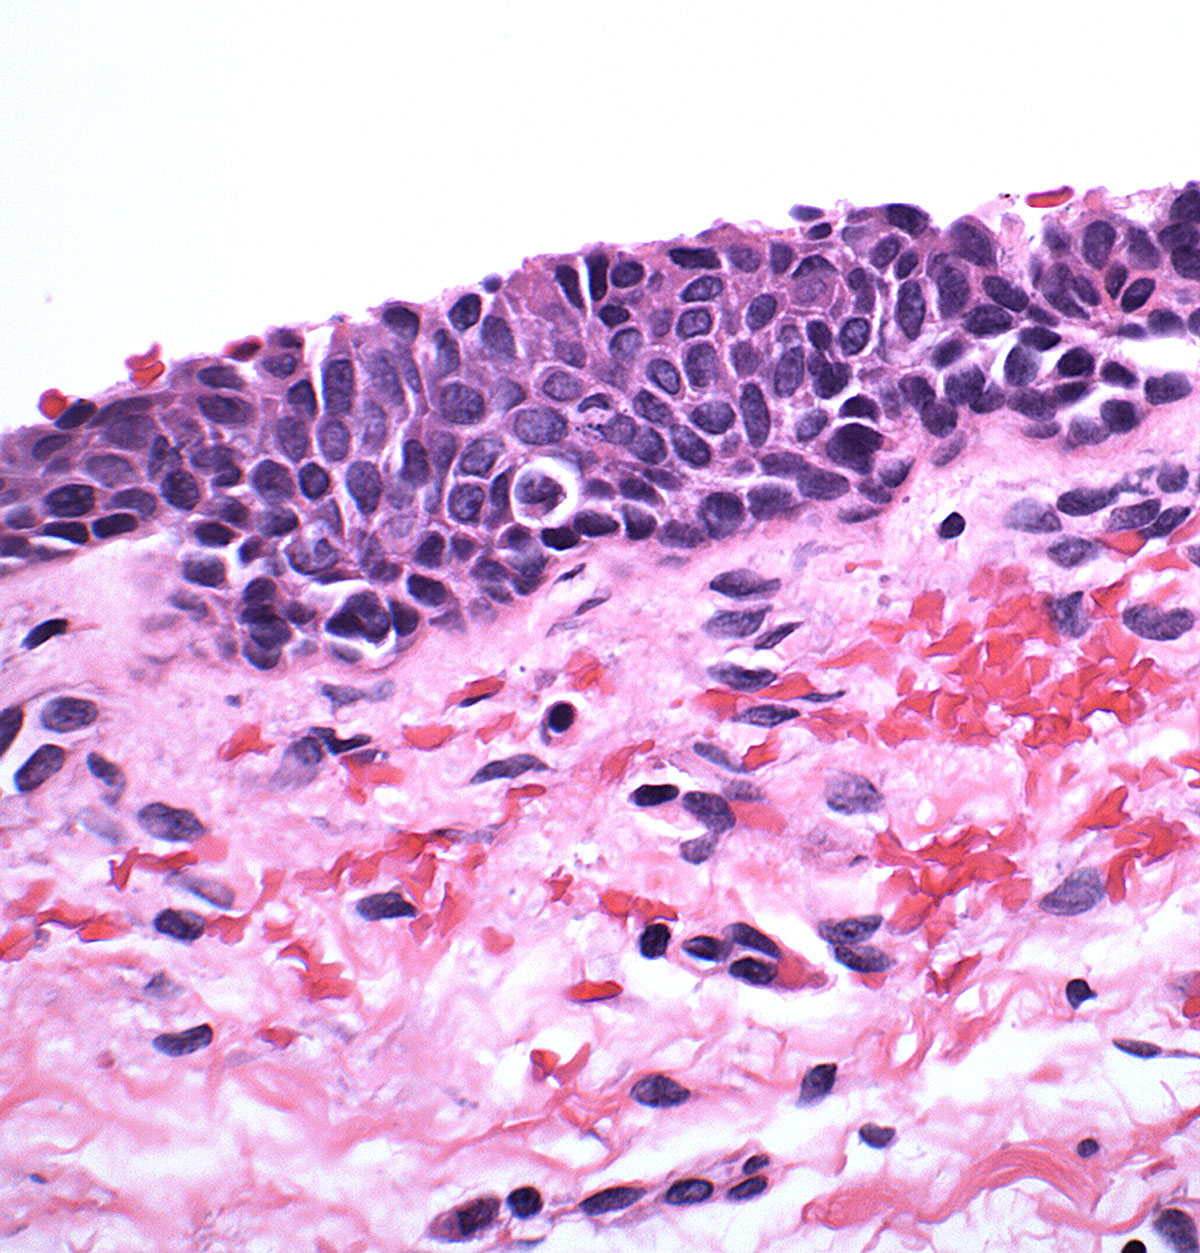

Understand the diagnosis and treatment of a Dieu La Foy lesion, a rare cause of severe gastrointestinal bleeding. Learn how this submucosal vessel anomaly leads to sudden hemorrhage and discover modern endoscopic management techniques, including clipping and coagulation, essential for clinical intervention. Improve your knowledge of this critical vascular pathology and its effective medical protocols for patient safety.